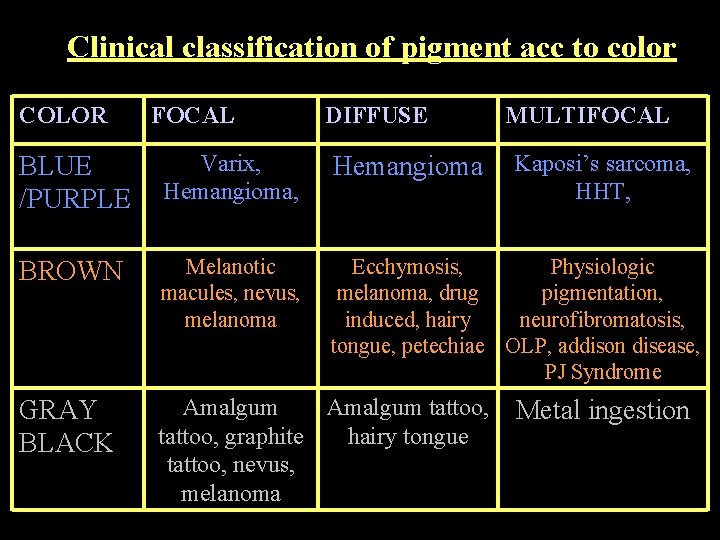

Clinical classification of pigment acc to color COLOR FOCAL DIFFUSE MULTIFOCAL BLUE /PURPLE Varix, Hemangioma, Hemangioma Kaposi’s sarcoma, HHT, BROWN Melanotic macules, nevus, melanoma Ecchymosis, Physiologic melanoma, drug pigmentation, induced, hairy neurofibromatosis, tongue, petechiae OLP, addison disease, PJ Syndrome GRAY BLACK Amalgum tattoo, graphite hairy tongue tattoo, nevus, melanoma Metal ingestion